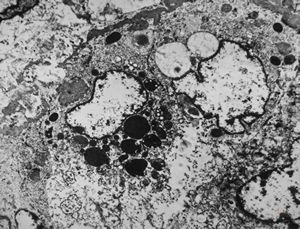

M,43y. | blood - degraded Candida (bone marrow suppression)

M,18y. | blood - clin. susp. leukemia - degraded Candida